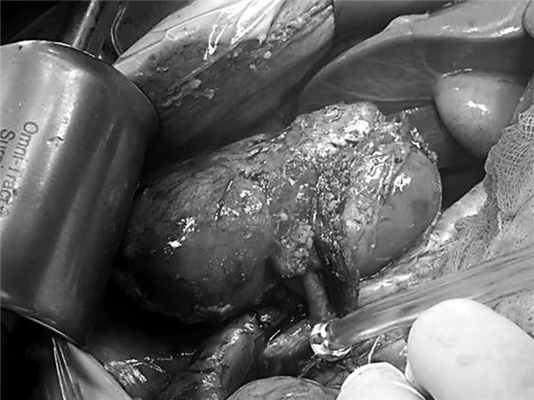

Таким образом, через 3 мес после исходной травмы произведена срединная лапаротомия. При ревизии в брюшной полости выявлен умеренно выраженный спаечный процесс. Правая почка крупных размеров, полностью вовлечена в воспалительно-рубцовый конгломерат, область ворот также представлена рубцовой тканью, окружающей сосудистую ножку, лоханка не дифференцируется. Визуально диаметр почечной артерии в 3—4 раза меньше, чем диаметр вены — около 3,5 мм (рис. 4). Рис. 4. Правые почечные артерия и вена после их диссекции.

Правый мочеточник, деформированный периуретеральными сращениями, прослеживался от мочевого пузыря до нижнего полюса почки, далее превращался в плотный тяж, лишенный просвета. Протяженность этого участка до 5 см. С учетом полученных данных решено отказаться от попыток восстановить длину мочеточника путем пластики собственными тканями. Облитерированная часть мочеточника резецирована, проходимость оставшегося дистального отдела подтверждена с помощью контрастной пробы. Почка с трудом мобилизована из сращений (при этом потребовалась ее частичная декапсуляция), почечные сосуды пересечены, начата процедура холодовой ишемизации органа с перфузией раствором для кардиоплегии. После извлечения из брюшной полости почка помещена в емкость с ледяным физиологическим раствором для дальнейшей подготовки к пересадке. На данном этапе определенную сложность представляла идентификация редуцированной лоханки, которая располагалась внутрипочечно, а также поиск и выделение из рубцов зоны для последующей пиелоуретеростомии (рис. 5). Рис. 5. Редуцированная лоханка правой почки и место отрыва мочеточника (показано стрелкой). В целом холодовая ишемия органа продолжалась 55 мин.

Дальнейший ход операции не отличался от стандартного. Почку переместили книзу, перитонизацию не выполняли, оставив ее интраперитонеально. Сформированы анастомозы по типу конец в бок между почечными сосудами и правыми общими подвздошными артерией и веной, пиелоуретероанастомоз, полостная система дренирована внутренним JJ-стентом 6 Fr (рис. 6). Рис. 6. Общий вид почки после завершения аутотрансплантации.